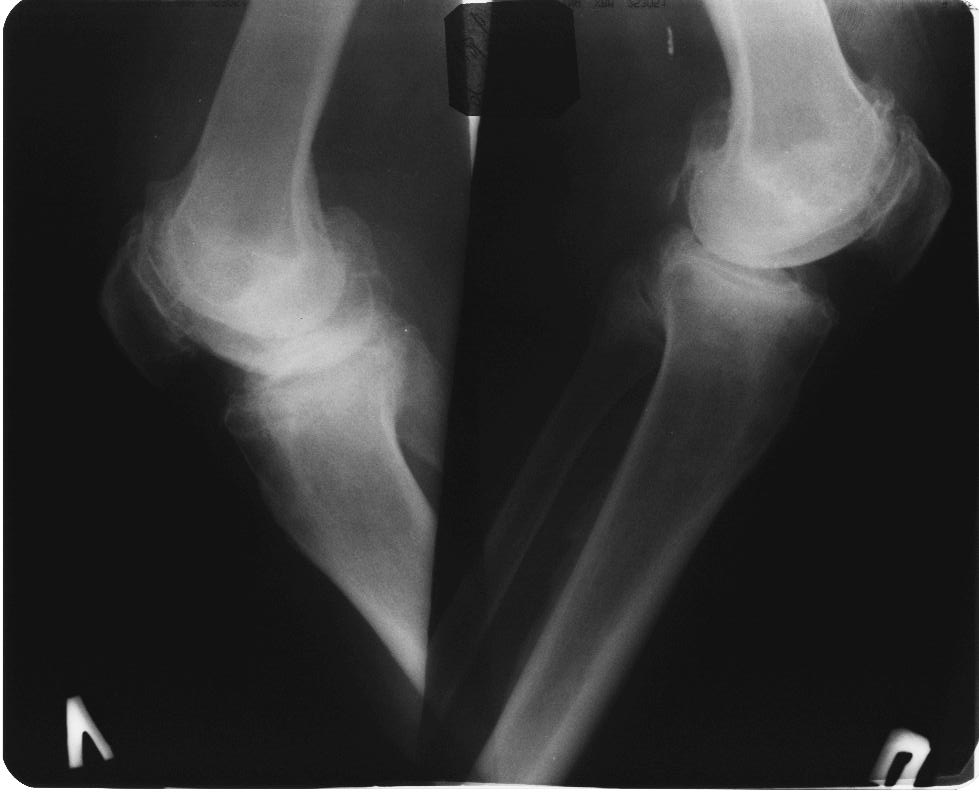

Лечение возможно до последнего вздоха пациента, без всяких хирургических агрессий. Не факт, что поможет. Если есть противопоказания к хирургии

вообще, то в комплекс симптопатической терапии входят всякие медикаменты + ИСЖ (гиалуронаты) + гормоны при "мокром" суставе + физиолечение + грязи + солнце - воздух и вода + доброе слово и участие доктора и все это.... не удел ортопеда -хирурга. Это ближе к терапии. Чуть агрессивнее различные артроскопические санации и манипуляции - временно помогает + ИСЖ + фиксаторы + ортезы + аппараты + трость и костыли + коляска. Однако судя по рентгенограммам - суставы приговорены к эндопротезированию.

Глядя на снимки, кроме оперативного лечения в голову ничего не приходит. Хотя бы корригирующая кортикотомия б/б кости с минимальной внешней фиксацией. Высылаю пример.

Я всячески поддерживаю тактику оперативного вмешательства. Но просто тема консервативного лечения, надеюсь Вы согласитесь, на форуме обсуждается КРАЙНЕ РЕДКО И НЕОХОТНО. А применительно к выложенным R-граммам, конечно, показано Эндопротезирование, но только заголовок обращения сразу расставляет приоритеты в пользу консервативных методик. Причины тому могут быть самые разнообразные, нам о них не сообщили. Так зачем же предлагать коллегам то, чего они делать не будут?